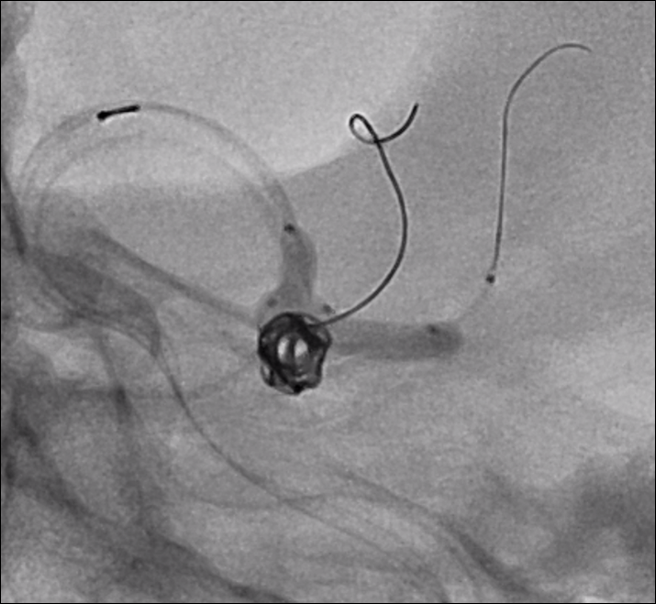

En este aneurisma se realizó la cateterización con dos balones de remodeling Eclipse 2L con microguías Traxcess y Ashahi .014, realizando dos cambios de curva para el cateterismo distal. El acceso proximal se realizó con un introductor largo Ballast .088 de 90cm que permite el uso de dos balones y un microcatéter para introducir los coils.

Con un buen posicionamiento de los balones se logró el cierre completo del aneurisma con seguridad y control garantizando la permeabilidad de las ramas. En este caso no se completó el tratamiento con stent por que la paciente debe someterse a una cirugía reciente.